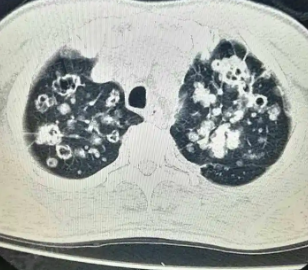

肺上有空洞是否严重需要根据具体病因、病情进展以及治疗情况来综合判断。对于肺结核和肺脓肿引起的空洞,经过积极治疗大多可以愈合,病情相对较轻;而肺癌引起的空洞则可能较为严重,尤其是晚期肺癌,一旦发现肺上有空洞应及时就医,明确病因并接受针对性治疗。

- 肺结核:肺结核患者的肺部会出现干酪样坏死,当坏死物排出后会形成空洞。针对肺结核,目前主要是通过抗结核药物进行治疗,一般经1年左右的正规治疗,大多数病情可得到控制,空洞也可愈合,因此这种情况并不十分严重,也不影响患者的寿命。

- 肺脓肿:肺脓肿是由细菌感染后,脓肿向外溃破形成的空洞。肺脓肿产生的空洞经积极抗感染治疗,并注意痰液引流,使炎症得到控制,空洞也可愈合,这种情况同样不十分严重。

- 肺癌:肺癌也可造成肺空洞,主要是由于肿块生长速度较快,肿物内部因缺血坏死,坏死物液化并排出体外,形成空洞。癌性空洞的严重程度取决于肿瘤的恶性程度和分期。分期较早的肿瘤经积极治疗,5年生存率较高;但如果病情已经发展到晚期,5年生存率则比较低,且可影响患者寿命。

肺空洞的严重程度还与病情的进展速度有关,如果空洞迅速增大,伴有明显的咳嗽、咳痰、胸闷、呼吸困难等症状,且药物治疗效果不佳,可能提示病情较为严重。如果能够早期诊断并积极治疗,大多数肺空洞可以得到控制或愈合,从而减轻病情的严重程度。